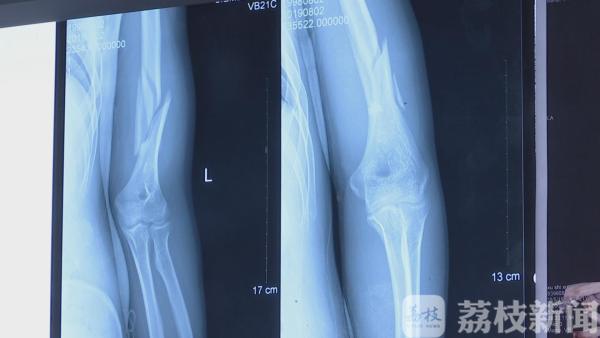

21号上午 , 采访人员从武进人民医院骨科了解到 , 8月7号晚上 , 120救护车送来了一名伤者 , 伤者姓许 , 是一名21岁的大学生 , 左手肱骨粉碎性骨折 。 据伤者说 , 是因为自己和朋友之间掰手腕比力气时受伤的 。

通过X片可以看出 , 伤者骨折极其明显 , 骨头断为两截 。 历医生表示 , 如此严重的骨折一般多出现在外伤事故中 。 此前也遇到过几例掰手腕受伤的 , 但像许同学这种粉碎性骨折 , 他从医近二十年来也是第一次看到 。